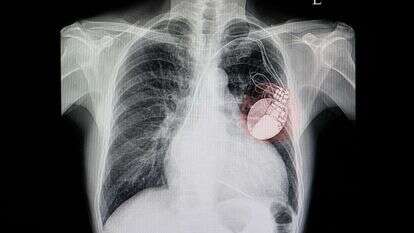

שבוע אחרי שדווח כי התייבש ונאלץ לעבור הליך להחדרת מנטר תת-עורי שיעקוב אחרי הדופק שלו, הלילה עבר ראש הממשלה בנימין נתניהו פרוצדורה להשתלת קוצב לב במרכז הרפואי שיבא-תל השומר. לפי הודעת הרופאים, מצבו טוב והוא מתאושש.

פרופ' דוד לוריא, מנהל היחידה לטיפול בהפרעות קצב לב וקוצבים במרכז הרפואי הדסה עין כרם, שנחשב לאחד הקרדיולוגים המומחים והבכירים בארץ, מסביר את ההליך שעבר ראש הממשלה במהלך הלילה: "מדובר בהליך להשתלת מכשיר שמונע את ירידות דופק הלב ומתקן את הבעיה שגורמת לתחושה רעה ולעלפון".

לדבריו, יש כיום שתי שיטות להחדרת קוצב הלב לגוף. הראשונה והוותיקה יותר נעשית בניתוח ("קטן אבל עדיין עם חתך, תפרים וחוט בתוך הלב") וההליך השני נעשה ללא התערבות כירורגית ונקרא "MICRA" - קוצב ללא חוטים שמושתל בצנתור דרך הווריד. "ההליך שעשו לראש הממשלה הוא האופציה השנייה. זה הליך שנמשך בין חצי שעה לשעה ובהרדמה מקומית וטשטוש. מדובר בפרוצדורה בטוחה ולא מסובכת ועם סיכון קטן של פחות מאחוז אחד של סיבוכים. זה מאפשר טיפול מאוד מדויק שנותן ללב יכולת לעבוד בצורה טובה ובקצב נורמלי".